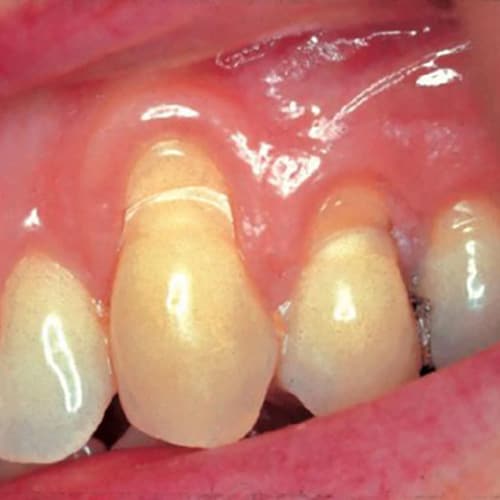

Localized Recession And Abrasion